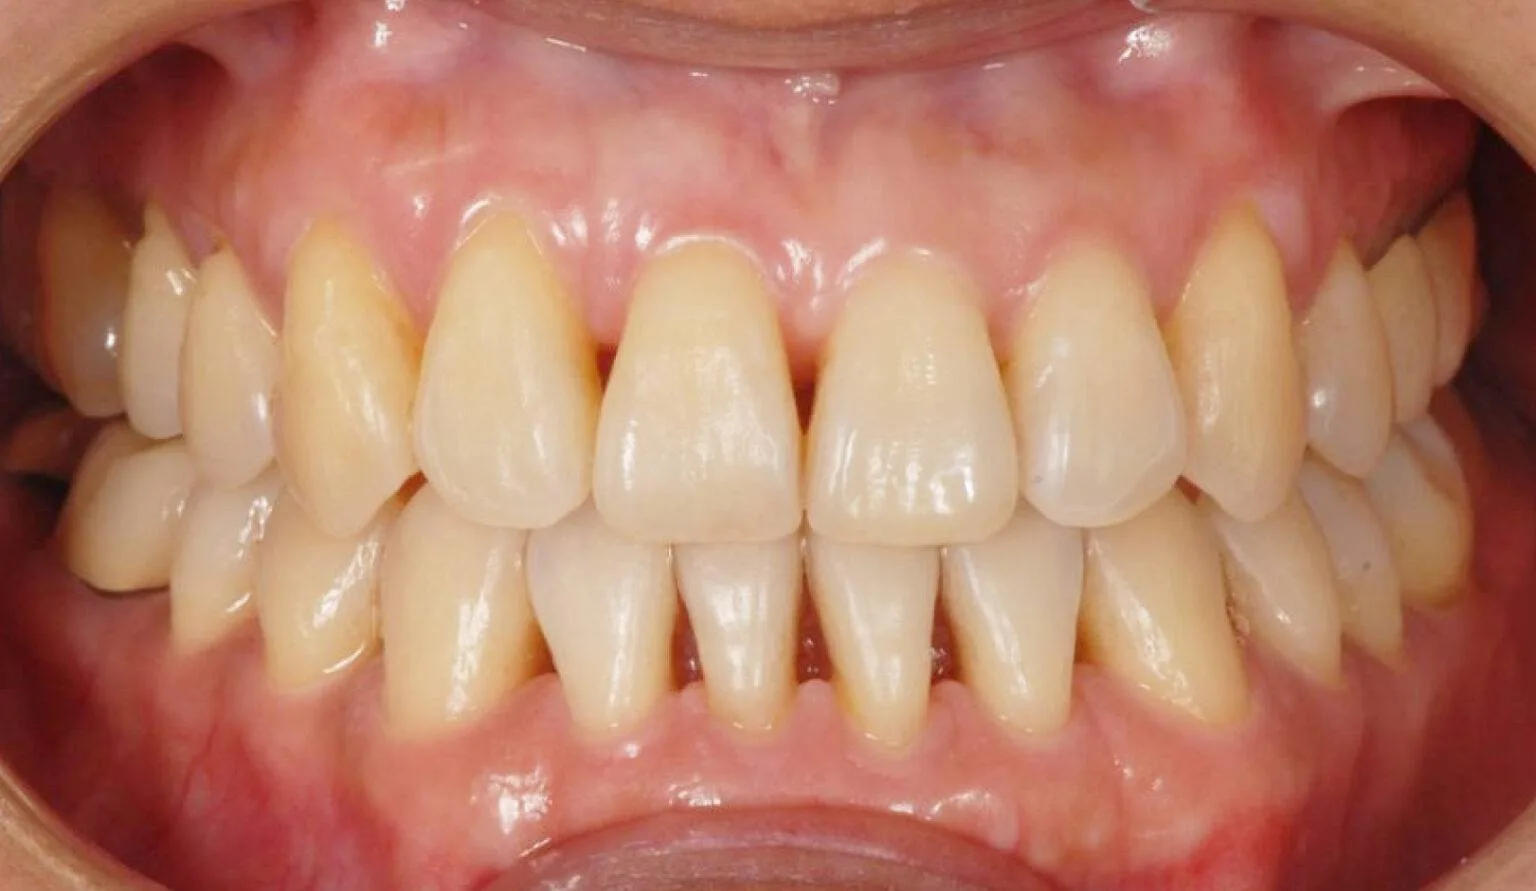

Before & After Invisalign® Gallery